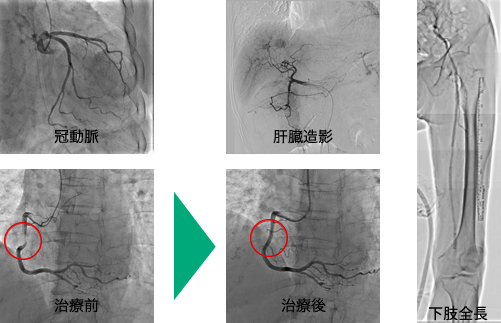

血管造影検査

カテーテルという細い管を腕や太ももの付け根の血管から目的血管まで挿入し、造影剤を使用して撮影し必要に応じて治療まで行います。血管が狭くなったり、詰まったりしていないかなど血管自体、また血管が関与している疾患を詳しく調べ、必要があればIVRと呼ばれる血管撮影手技を応用した治療、例えば心臓の冠動脈に対するバルーン治療やステント挿入術・肝臓癌の血管塞栓術や動注療法などを行っています。

当院の血管造影撮影装置は、FPD(フラット・パネル・ディテクター)と呼ばれる検出器を搭載している為、従来より診断能力の高い鮮明な画像を提供する事が可能になりました。また、従来の装置は心血管のみが対象でしたが、腹部血管、下肢血管も造影の対象になりました。詳しい内容は医師へお気軽にお尋ね下さい。